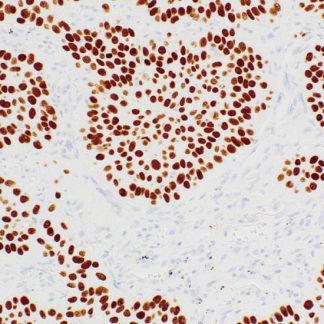

Cytokeratin 20 Antibody (Immunohistochemistry)

The Cytokeratin 20 (CK20) Antibody is a specific and widely used IHC marker.

It helps detect and differentiate epithelial tumors, especially those originating from

the gastrointestinal and urinary tracts. In addition, CK20 is an intermediate filament protein

expressed in gastric and intestinal epithelium, urothelium, and Merkel cells.

Moreover, CK20 shows strong positivity in adenocarcinomas of the colon, stomach, pancreas,

and biliary tract, as well as in Merkel cell carcinoma.

As a result, its staining pattern becomes a reliable tool for determining tumor origin.

- Clear brown cytoplasmic staining in positive cells